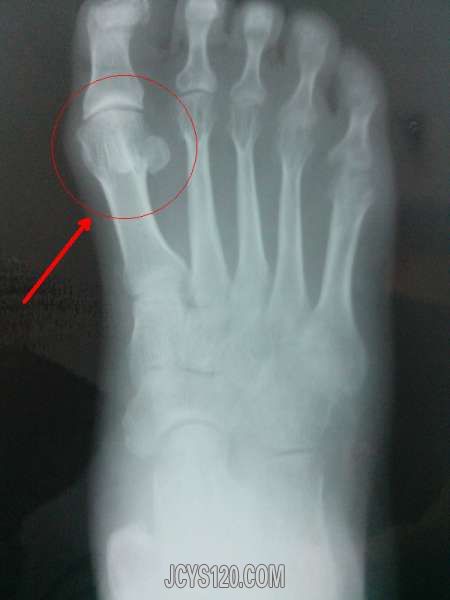

患者,男性,60岁,轻度智力障碍,能回答简单问题,一周前跟家人叙述右脚疼痛,发现其右脚轻度肿胀,局部皮肤无颜色改变,局部压痛,压痛位置位于第一跖骨。

拍片如下,请问第一趾骨和第二趾骨之间有一圆形,密度跟骨骺差不多,上图吧,请问这是什么疾病?